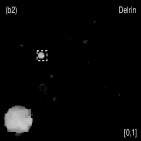

III.3 Catphan©600 phantom study

We acquired the Catphan©600 phantom data on a tabletop cone-beam CT (CBCT) system whose geometry matched that of a Varian On-Board Imager (OBI) on the Trilogy radiation therapy machine. We inserted iodine solutions with nominal concentrations of and into the phantom. There were pixels with a physical size of per pixel on the CB4030 flat-panel detector (Varian Medical Systems). The DECT measurements were obtained at kVp and kVp with a tube current of mA and a pulse width of ms. We acquired projections over in each scan. Using a fan-beam geometry with a longitudinal beam width of on the detector niu2010shading , We acquired projections with scatter contamination inherently suppressed. We used a contrast rod slice of the Catphan©600 phantom to evaluated the proposed method. We reconstructed attenuation images of size with a pixel size of . Fig. 3 shows the low- and high-energy CT images. Fig. 3(a) identifies the rods with labels: Teflon (labeled as ), Delrin (labeled as ), Iodine solution of (labeled as ), Polystyrene (labeled as ), low-density Polyethylene (LDPE) (labeled as ), Polymethylpentene (PMP) (labeled as ), Iodine solution of (labeled as ). Fig. 3(b) shows selected basis materials and ROIs in white dashed line circles: Teflon (ROI1), Delrin (ROI2), Iodine solution of (ROI3), PMP (ROI4), Inner soft tissue (ROI5) and Air (ROI6).

Fig. 4 shows the decomposed material images by the Direct Inversion, the PWLS-EP-LOOP and the PWLS-TNV- method. The left corners of the to the column of Fig. 4 show enlarged rods that are highlighted with white dashed boxes in decomposed material images. Table 2 summarizes the means and noise STDs of ROIs of decomposed basis material images. The volume fraction (VF) accuracies were , , and for the Direction Inversion, the PWLS-EP-LOOP and the PWLS-TNV- method, respectively. Compared with the Direct Inversion and the PWLS-EP-LOOP method, the proposed PWLS-TNV- method increases the VF accuracy by and respectively.

Table 3 summarizes the average electron densities of contrast rods and RMSE() of electron density for the three MMD methods. The RMSE() was , and for the Direct Inversion method, the PWLS-EP-LOOP method and the proposed PWLS-TNV- method, respectively. The proposed PWLS-TNV- method suppressed noise, decreases crosstalk and increased decomposition accuracy in the material images, while maintaining high image quality.